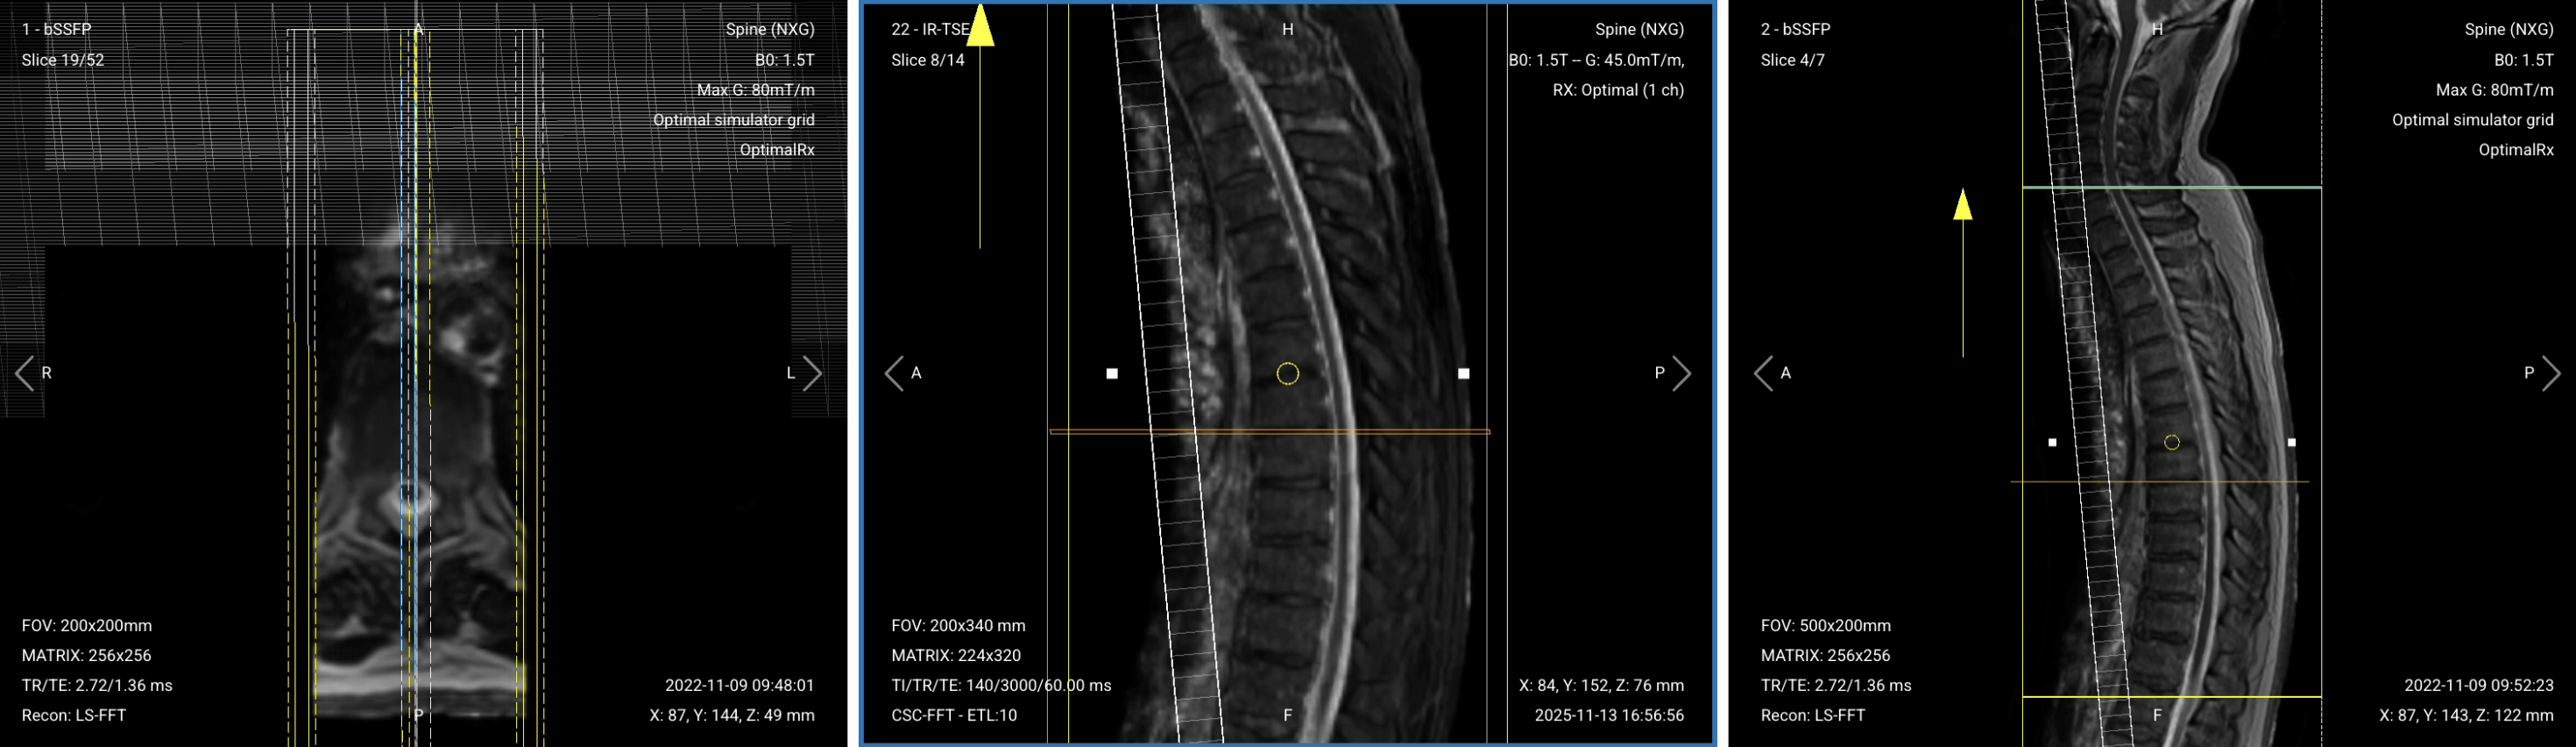

Before we can perform any MRI protocol, we must always capture initial localizer images of the patient. These images act as a guide for planning the detailed scans we will perform next.

We should always capture localizers in three planes:

Once acquired, upload the initial localizer images into the three viewports.

Then, scroll through each of the image stacks to locate a central slice that clearly shows the anatomy of the thoracic spine.

✅ Correct Setup of Localizer Images for Thoracic Spine MRI: